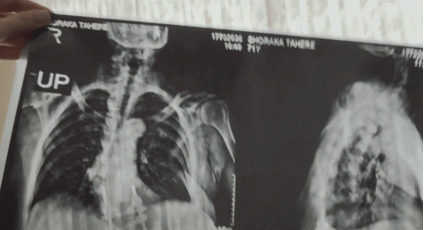

El factor histórico del asesinato del Dr. Alí Shariati, que lo convirtió en mártir y unos de los factores de unión de la población para derrocar al gobierno del Sha, en la obra de Firouzeh desencadena nuevas imágenes «veladas» (Figura 15, 16, 17 y 18) con relación a la participación de las mujeres como parte de las fuerzas militares de la Revolución de Irán y posteriormente jugando un papel activo igualmente en la Guerra contra Irak que inició en 1980 y culminó en 1988.

De estas imágenes de la figura anterior, en la capa de fondo se generan las emociones de la directora que expresan el miedo de perder a su madre y la ausencia de ella en casa por su militancia activa al servicio del nuevo régimen islámico, esto en un sentido relacionado con la infancia de la directora y el momento tan complejo de infancia que ella vivió… pero adicionalmente caben nuevas preguntas, ¿qué representa este doble velo que es evidente en estas imágenes, el de la propia imagen y el que les cubre en la vestimenta? ¿El símbolo de la resistencia femenina, la religión y la forma de reclamar su lugar en su mundo? ¿Qué es lo que cubre y qué es lo que deja ver como espectadores?